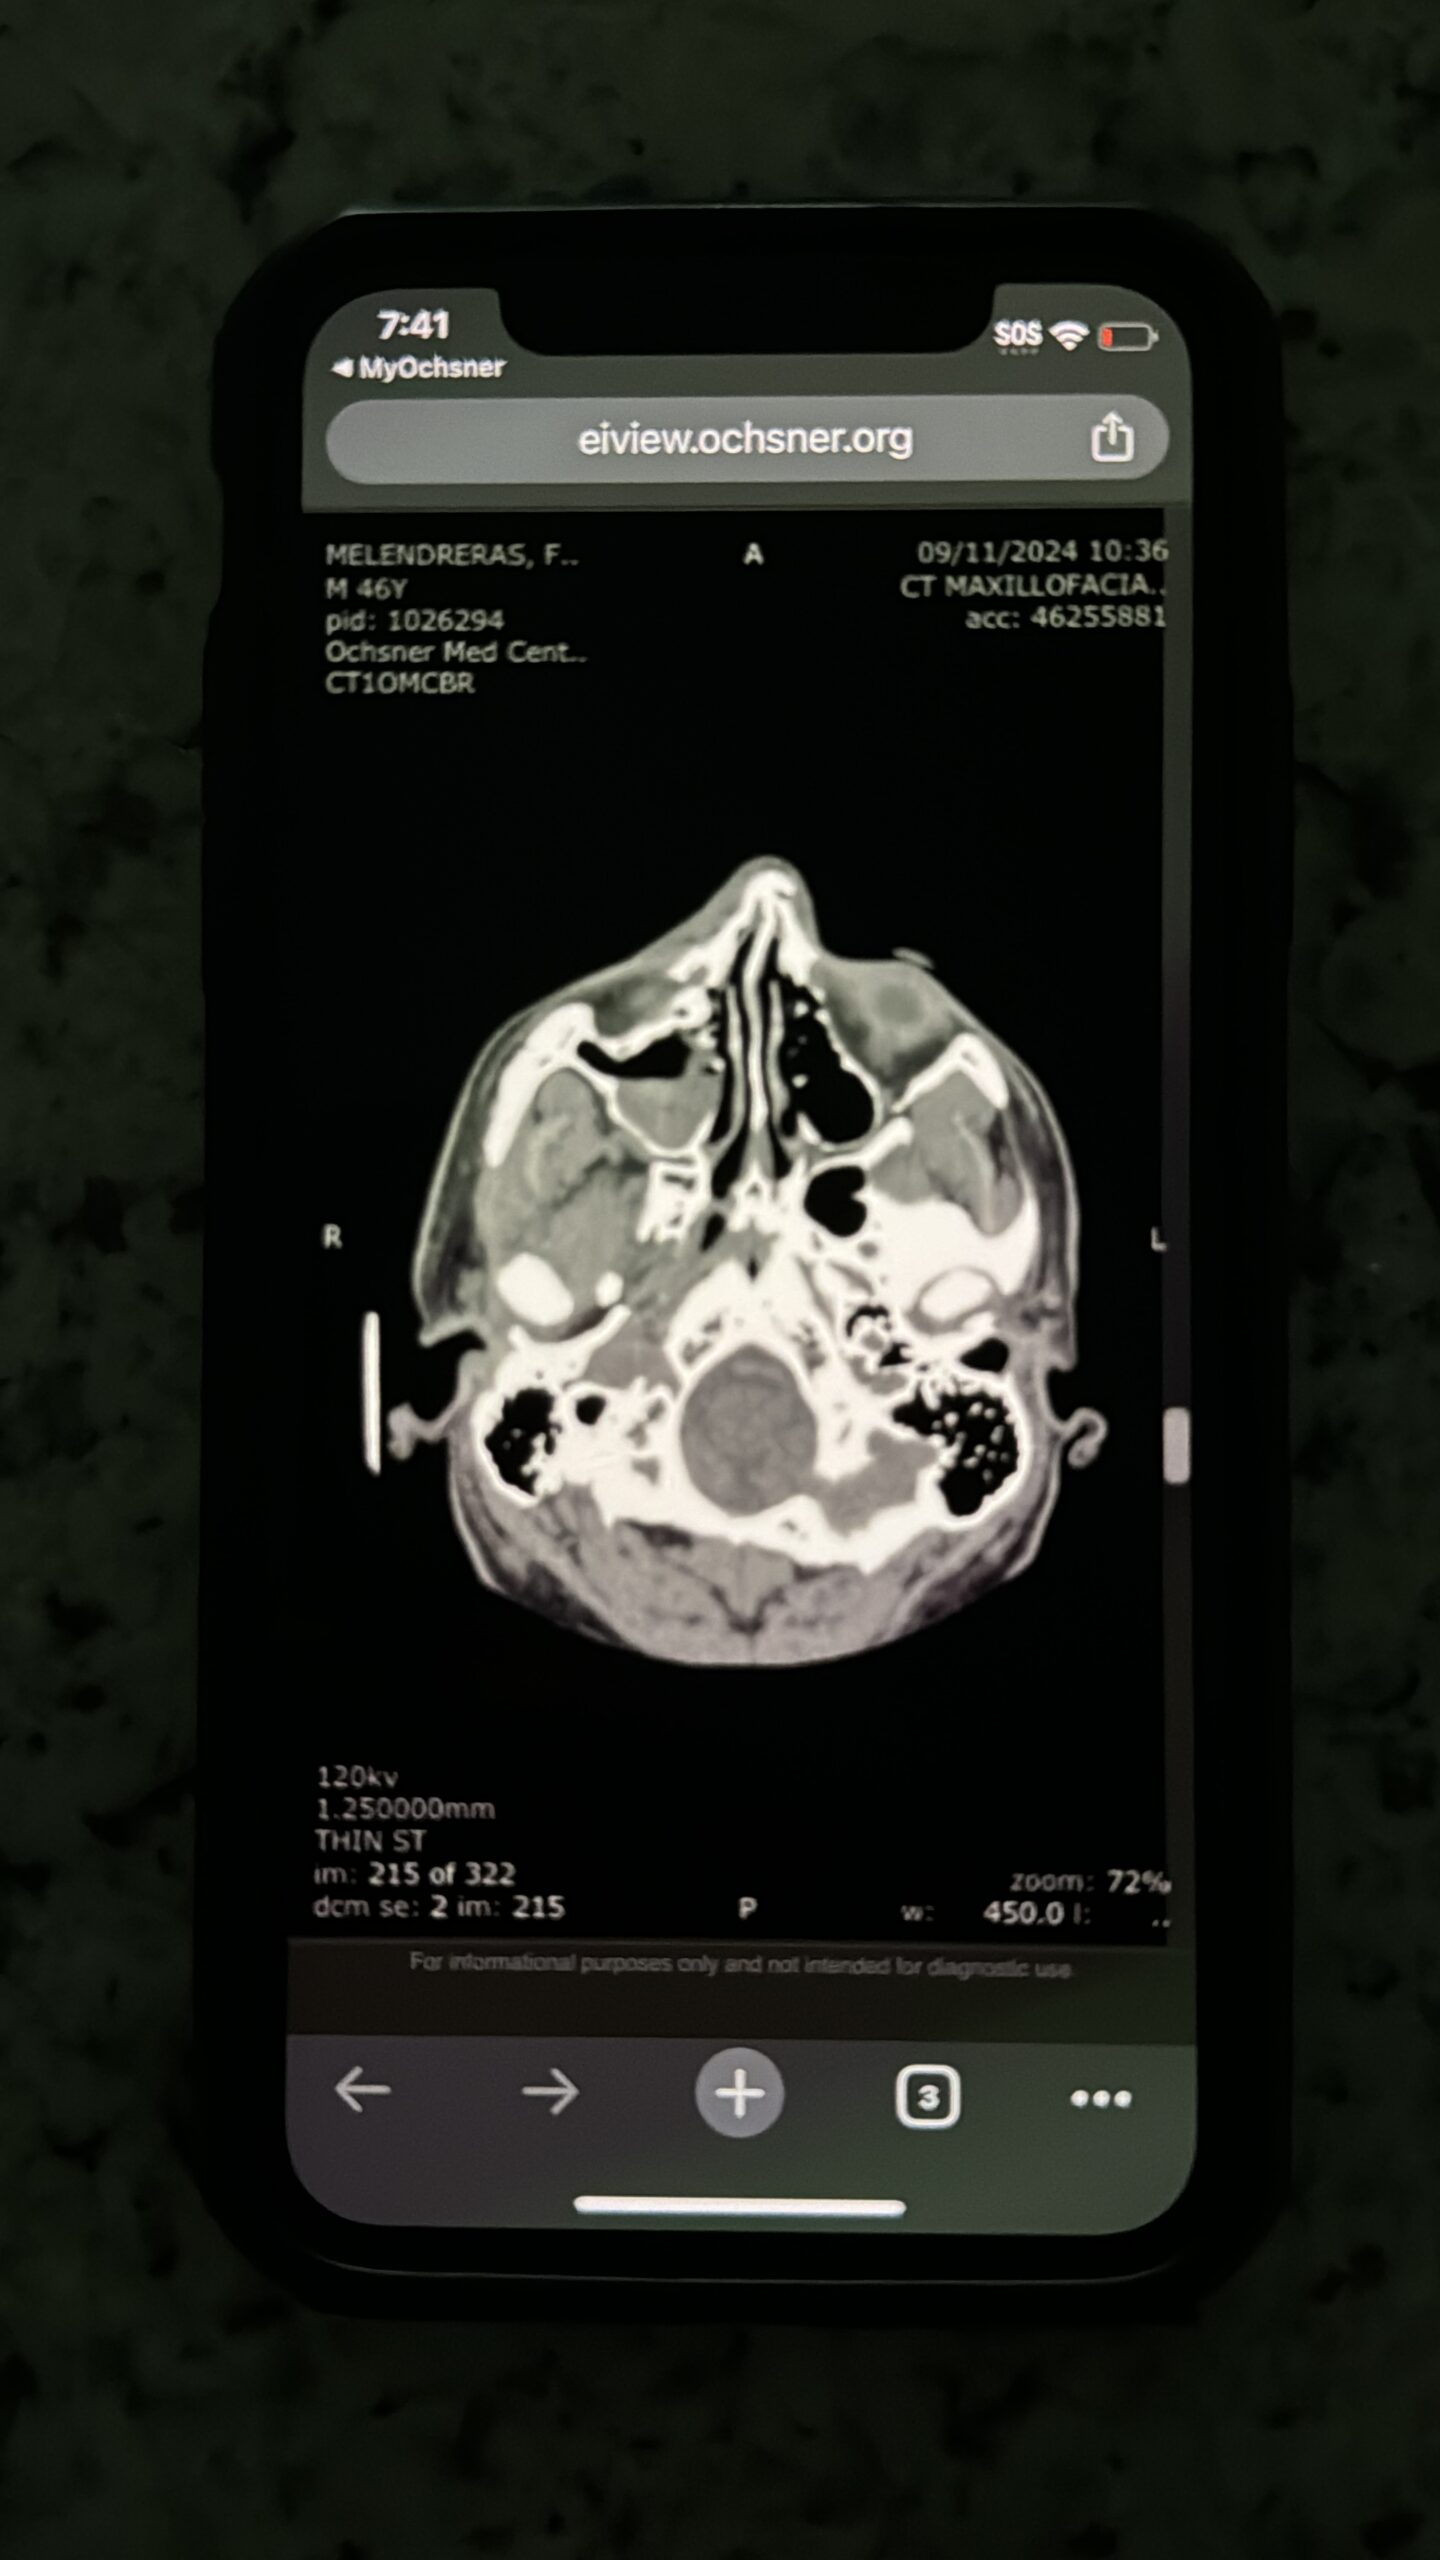

Tests began immediately, as the visible injuries—the broken nose, the bruising—pointed to undeniable battery. Yet somehow, the system treated it as another ordinary skirmish, all while the man who attacked him continued to stroll around the neighborhood freely, gun in tow.